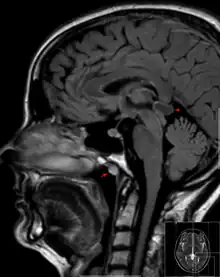

| Tornwaldt cyst imaged on sagittal MRI (FLAIR). The cyst appears hyperintense in the midline of the nasopharynx (arrow). In this case there is also a cyst of the pinealis gland (arrowhead) showing a signal intensity slightly higher than the CSF. | |

A Tornwaldt cyst also spelt as Thornwaldt or Thornwald cyst[1] is a benign cyst located in the upper posterior nasopharynx. It was first described by Gustav Ludwig Tornwaldt. It can be seen on computed tomography (CT) or magnetic resonance imaging (MRI) of the head as a well-circumscribed round mass lying in the midline. In most cases, treatment is not necessary. Indications for treatment include symptomatic lesions, large lesions (>1 cm), or lesions adjacent to the eustachian tube orifice.[2]